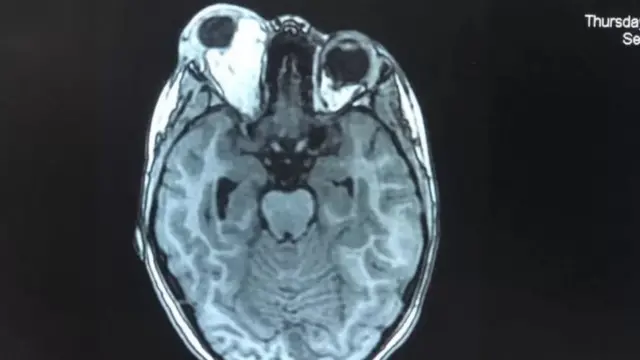

یاسمین کے ایکسرے کیے گئے، سی ٹی سکین اور ایم آر آئی ہوئے۔

،تصویر کا ذریعہLITTLE PRINCE HOSPITAL